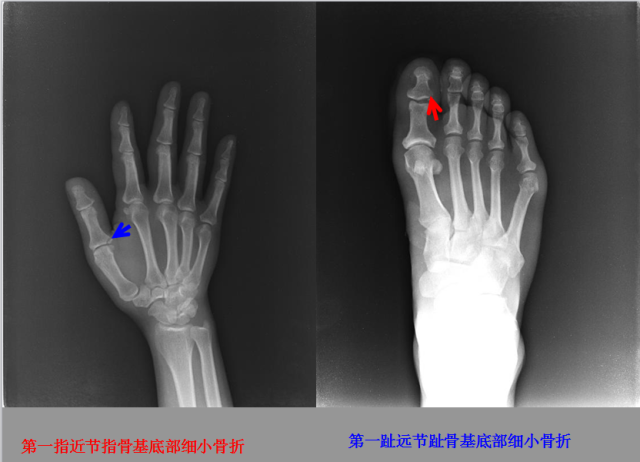

骨折篇

01

定义:骨折{Fracture}是指骨的完整性和连续性的折裂或粉碎。包括创伤性骨折、疲劳性骨折和病例理性骨折。 临床上以创伤性骨折*常见。